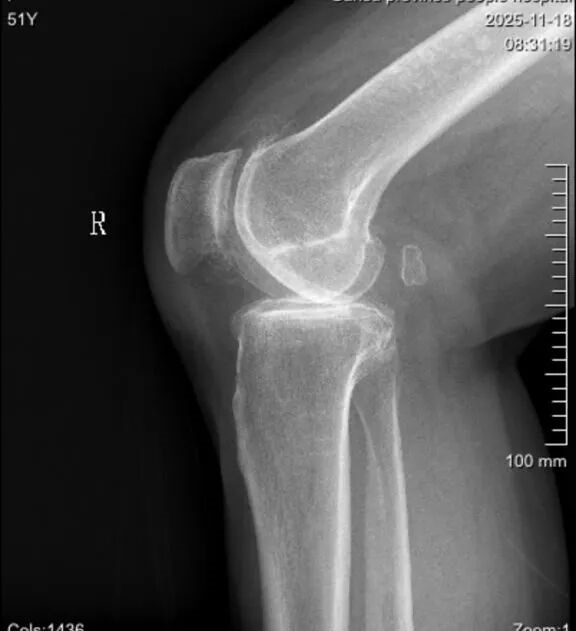

接受手术的5位患者均被诊断为重度膝关节骨性关节炎,且病情复杂多样,涵盖了严重内翻畸形、屈曲挛缩、外翻畸形及伴有骨质缺损等具有代表性的复杂病例,采用传统TKA手术挑战较大。

▲术前术后影像对比

▲影像对比

术前,手术团队根据患者CT影像数据进行三维建模与虚拟手术规划,精确设定“仿生内轴膝”假体的型号、安放位置、角度及截骨量,并前瞻性地在虚拟空间中模拟了截骨后的软组织平衡状态。术中,在鸿鹄®机器人的实时导航与视觉引导下,郭洪章主任操控轻量化灵巧机械臂,为不同畸形的患者执行了“量体裁衣”式的精准截骨。实时数据显示,鸿鹄®机器人在纠正严重内外翻力线、平衡屈曲与伸直间隙等关键步骤上,展现出超越传统工具和人眼判断的超高精度与稳定性,确保了“仿生内轴膝”假体所追求的内轴稳定性与生理运动学特性得以完美实现,助力恢复患者膝关节的自然运动功能。术后,患者均感觉良好,疼痛感可控,并于当日在康复团队指导下进行早期功能锻炼,展现了精准手术驱动下的快速康复优势。